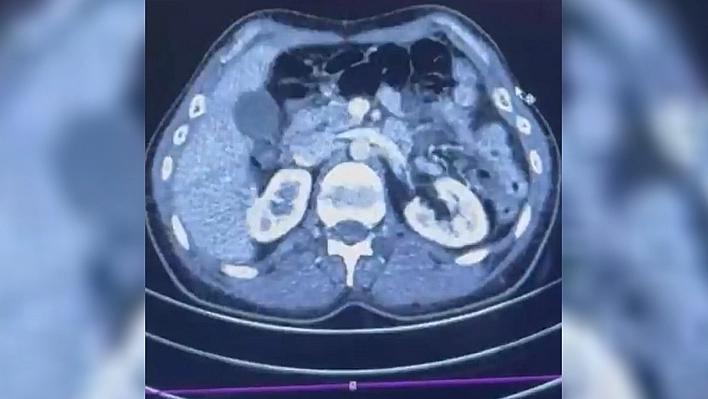

Edinilen bilgiye göre Narkotik Suçlarla Mücadele Şube Müdürlüğü ekiplerince uluslararası uyuşturucu madde ticareti yapan kurye şahıslara yönelik gerçekleştirilen çalışmalarda, İran’dan Türkiye'ye uyuşturucu madde getirdiği tespit edilen şüpheli şahısların yakalanması amacıyla operasyon düzenlendi. Düzenlenen operasyonda; S.C., R.B.C. ve G.M. yakalandı. S.C. ve R.B.C.'nin Kayseri Şehir Hastanesi'nde yapılan iç beden muayenelerinde, mide kısımlarında bulunduğu tespit edilen 50 adet kapsül şeklinde toplam 554 gram uyuşturucu madde ele geçirildi. Şüpheliler gözaltına alınarak haklarında 'Uyuşturucu Madde Ticareti Yapmak' işlem başlatıldı.